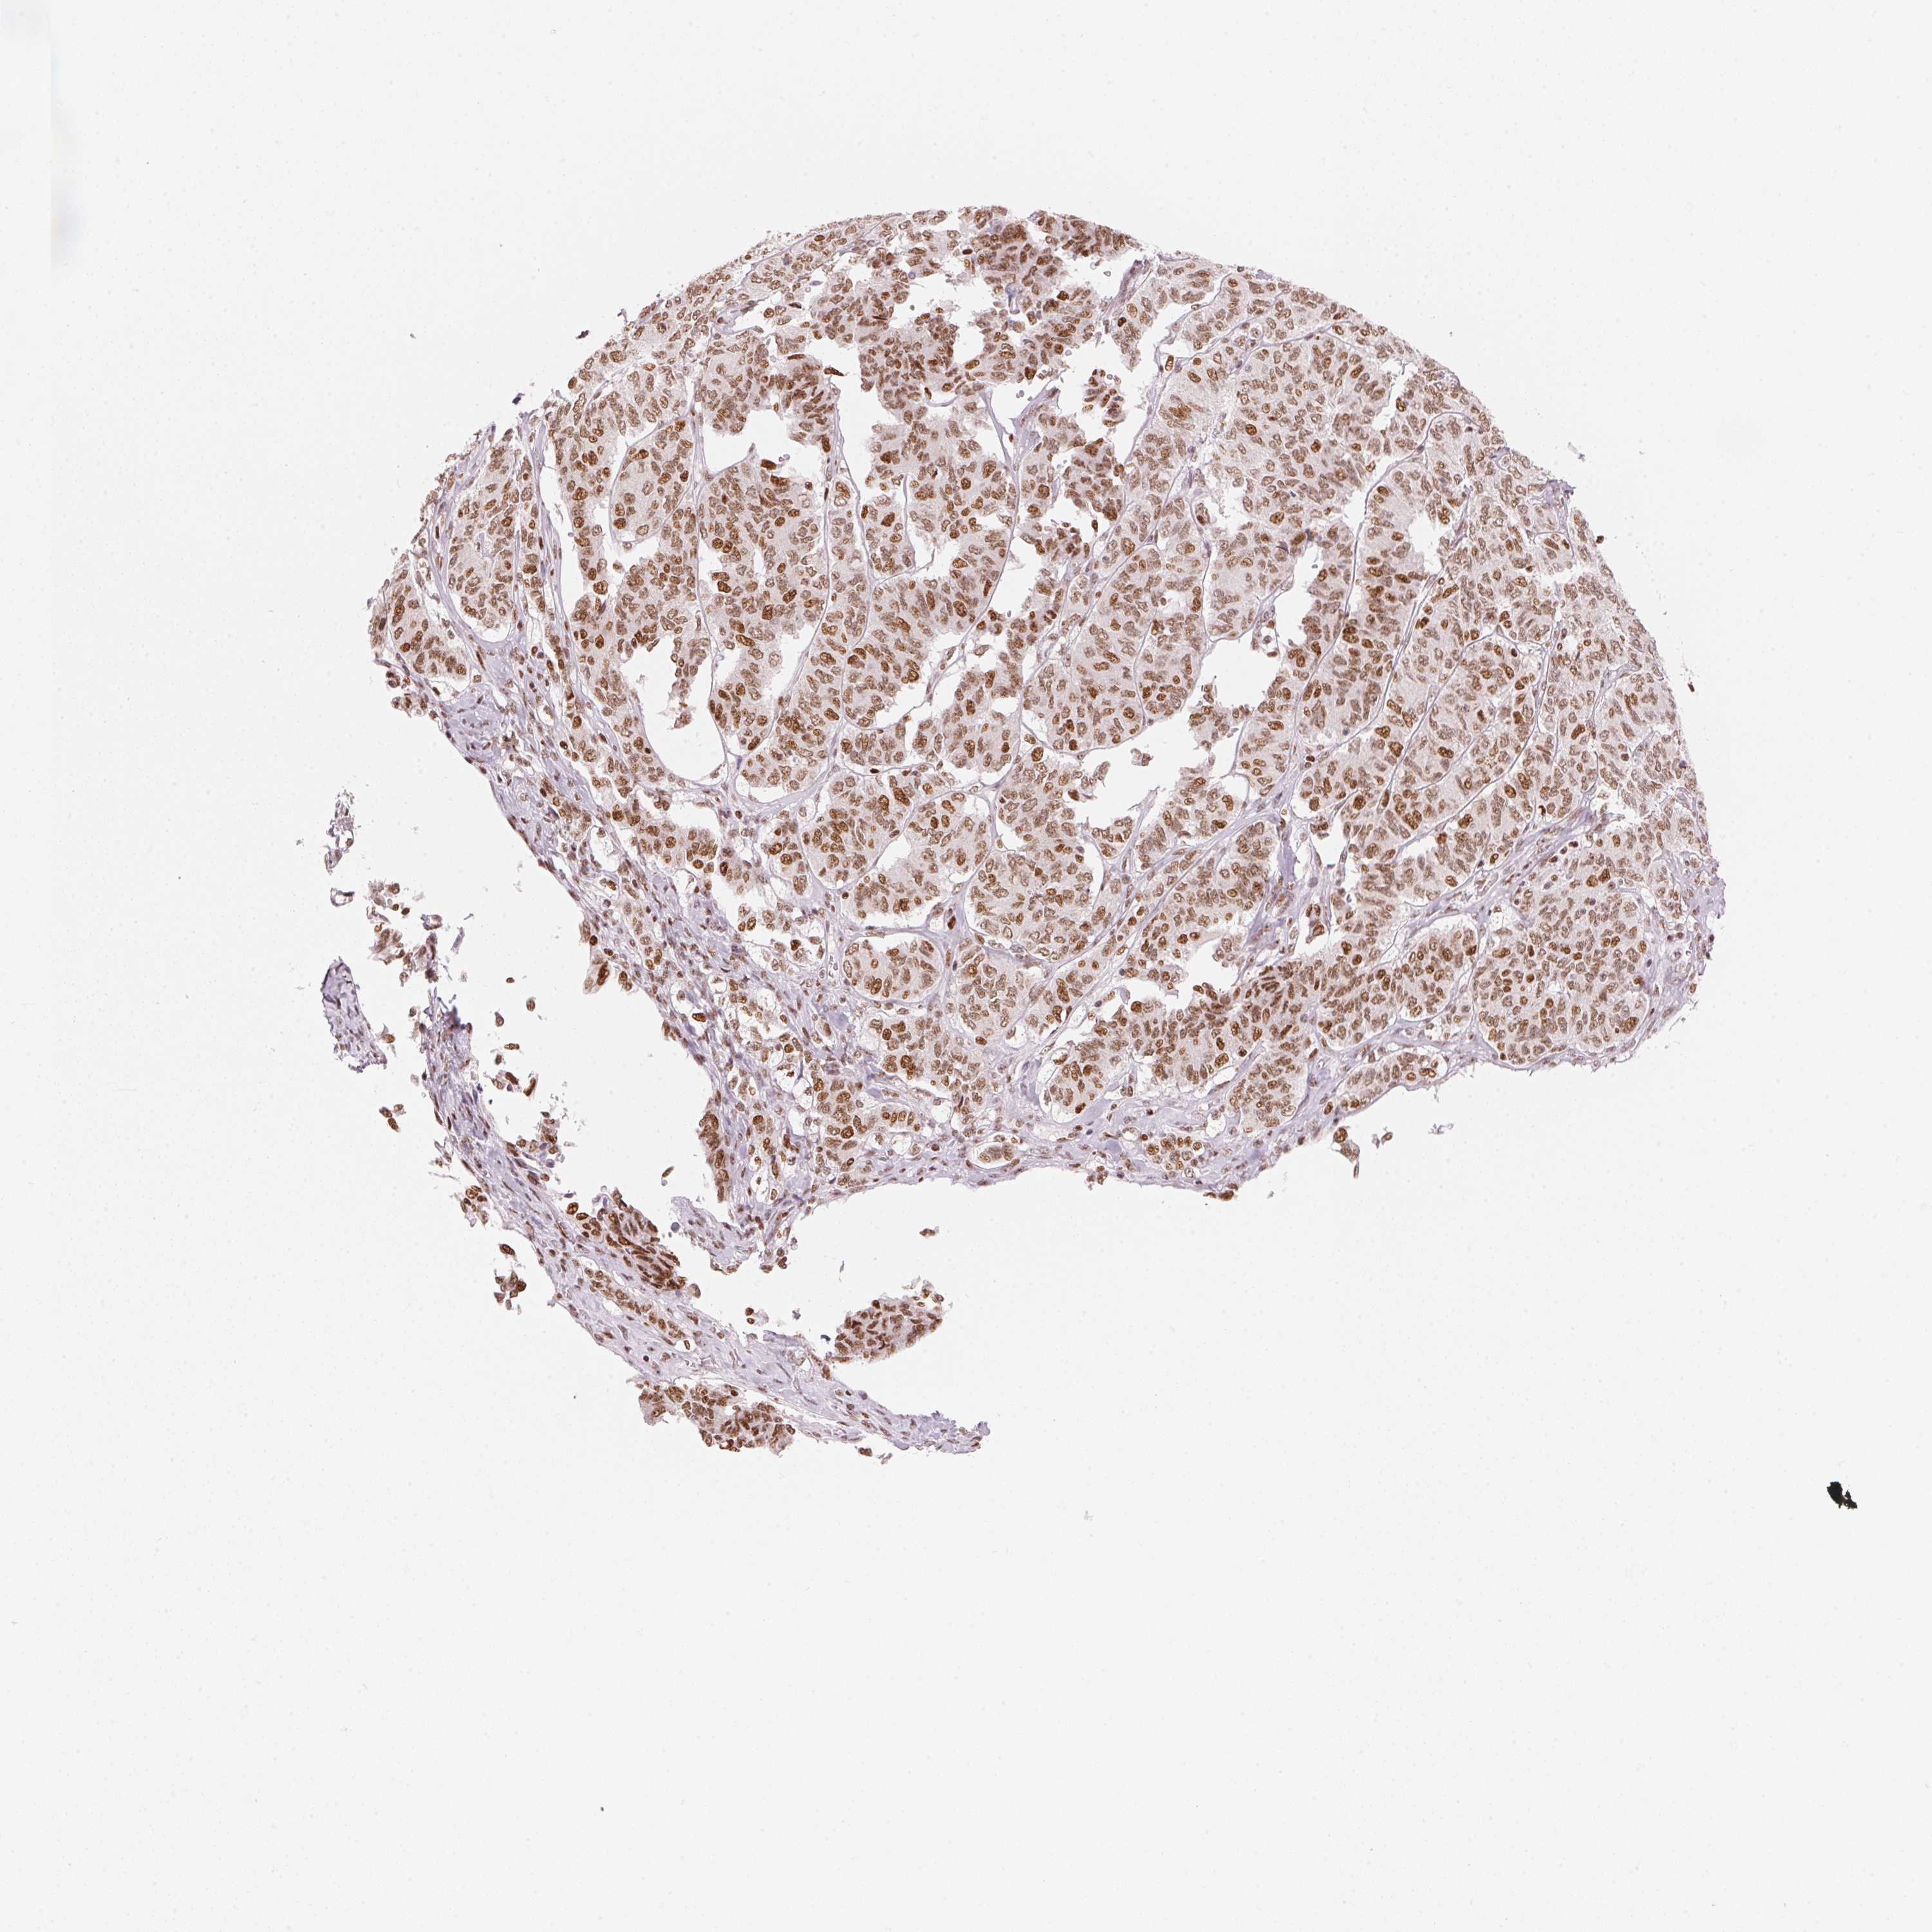

OVARIAN CANCER - Protein expressioni

A mouse-over function shows sample information and annotation data. Click on an image to view it in a full screen mode. Samples can be filtered based on level of antibody staining by selecting one or several of the following categories: high, medium, low and not detected. The assay and annotation is described here.

Note that samples used for immunohistochemistry by the Human Protein Atlas do not correspond to samples in the TCGA dataset.

Antibody stainingi

Antibody staining in the annotated cell types in the current human tissue is reported as not detected, low, medium, or high, based on conventional immunohistochemistry profiling in selected tissues. This score is based on the combination of the staining intensity and fraction of stained cells.

Each image is clickable and will lead to virtual microscopy that enables deeper exploration of all samples and also displays staining intensity scores, fraction scores and subcellular localization as well as patient and tissue information for each sample.

Antibody HPA061593

Antibody CAB016327

Staining

High

Medium

Low

Not detected

Intensity

Strong

Moderate

Weak

Negative

Quantity

>75%

75%-25%

<25%

None

Location

Nuclear

Cytoplasmic/membranous

Cytoplasmic/membranous,nuclear

Cystadenocarcinoma, serous, NOS

Cystadenocarcinoma, mucinous, NOS

Carcinoma, endometroid

Carcinoma, NOS